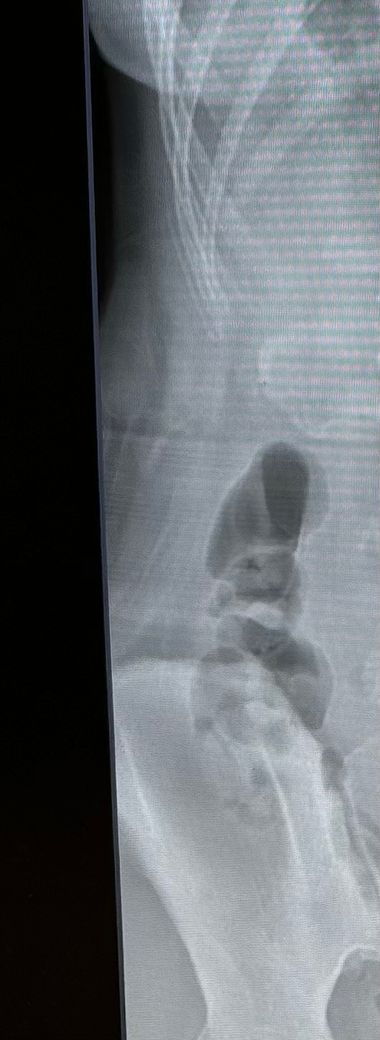

엑스레이 상으로 대장암을 알 수 있나요?

이건 변일까요...?ㅠ

요즘 속도 너무 안좋고 더부룩하고 ...뭔가 대장암 초기증상을 가지고있는것 같은데 대장암일까요??

• 1번 째 사진

엑스레이 사진으로 대장암을 진단하기는 매우 어렵습니다.

대장암이 걱정된다면 대장 내시경 검사와 복부 CT검사를 권합니다.

대장암은 엑스레이로 알기는 어렵습니다

보여주신 자료의 경우는 bowel gas입니다

횐자분이 원하는 질환을 확인하기 위해서는 일단 2가지 복부CT abdominal CT 대장내시경 colonoscopy가 필요합니다